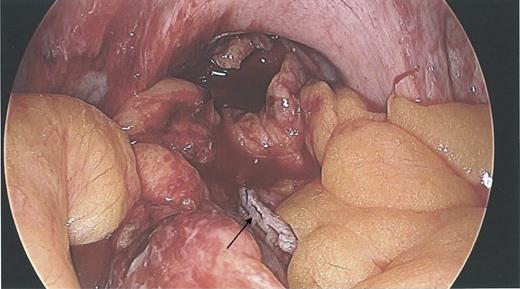

During the hysteroscopy 4 weeks later there was no evidence of an IUCD into the uterine cavity and no evidence of a perforation site in the uterus (Fig. 1). A laparoscopy followed, locating the coil threads deep in the Pouch of Douglas, with the IUCD perforating through the sigmoid colon into the lumen (Fig. 2). The IUCD was retrieved laparoscopically and the defect in the sigmoid colon was repaired by stapling the tear (Fig. 3).

Laparoscopy showing normal IUCD threads deep inside the Pouch of Douglas inside the sigmoid colon.